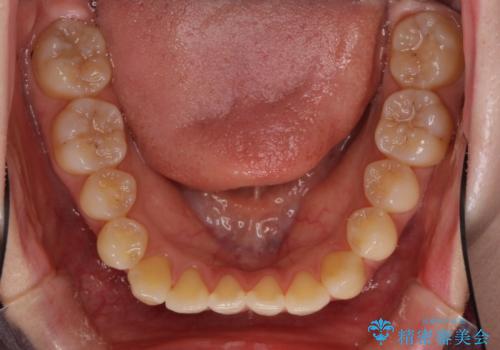

オープンバイトのインビザラインを用いた再矯正

- 矯正治療の後戻りを気にして来院された患者様です。

オープンバイト(前歯の開咬)と下顎骨の偏位による不正咬合が認められました。

骨格の偏位による不正咬合は改善しきれないことを理解いただいた上で、インビザラインにて矯正治療を行うこととしました。

オープンバイトは後戻りを起こしやすいため、極力そのリスクを軽減するため、奥歯を圧下させるように治療を進めていきました。

下顎骨の偏位が顕著であったため、上下の正中を合わせることはできませんでしたが、患者様には大変満足していただきました。